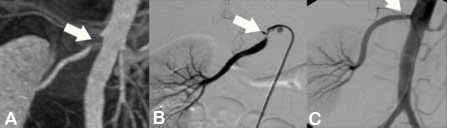

Abbildung:

Abbildung A zeigt eine MR Angiographie der Becken-Bein-Arterien bei einem Patienten mit Verschluß der Aorta infrarenalis sowie der Beckenarterien beidseits. Es besteht ein Zustand nach Anlage eines axillofemoralen Bypass sowie Anlage einer Links-Rechts-Umleitung. Auch die Oberschenkelarterien sind beidseits verschlossen.

Abbildung B zeigt eine MR Angiographie der Becken-Bein-Arterien bei einem Patienten mit Zustand nach Anlage eines femoropoplitealen Bypasses rechts. Darüberhinaus besteht ein Aneurysma der linken A. poplitea.